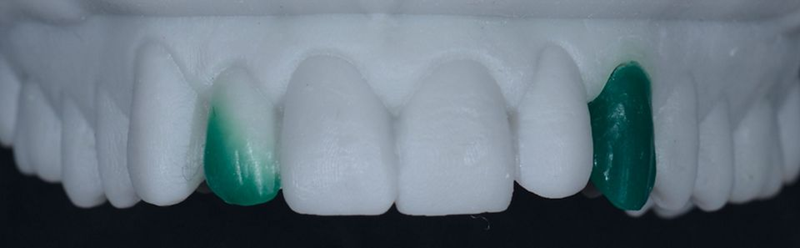

5. 牙科实验室基于数字蜡型(在树脂打印模型上)制作临时牙冠(图 22-24)。

Fig. 22: Lateral view of the printed model: Note that the shape of the provisional canine crown is now in line with the adjacent teeth.

Fig. 23: Provisional crown.

Fig. 24: The occlusal view shows the provisional abutment and...